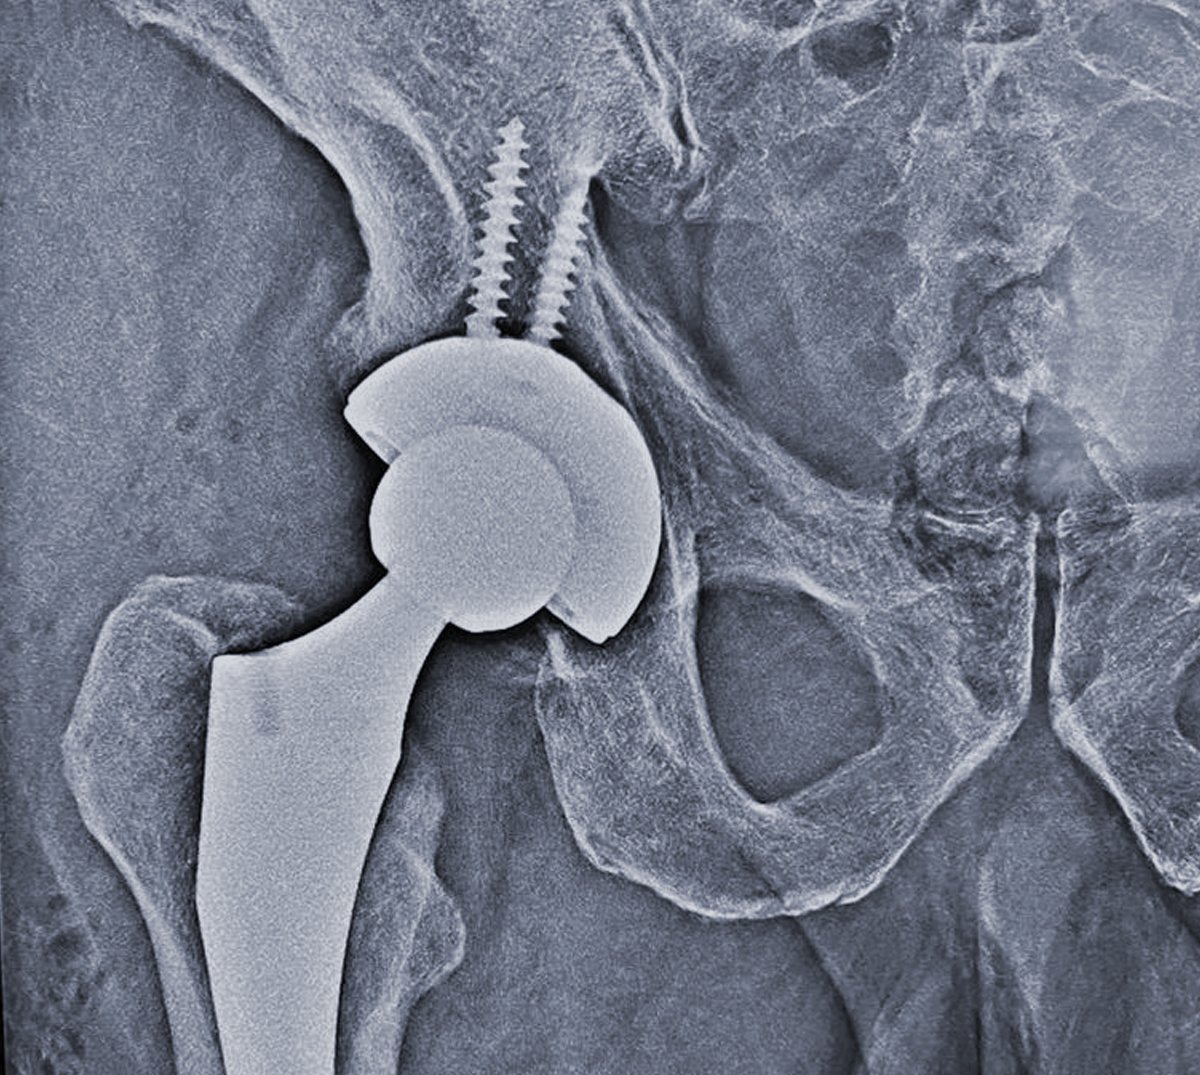

REEMPLAZO ARTICULAR

(HOMBRO, RODILLA Y CADERA)

Las prótesis son implantes ortopédicos que se colocan en el cuerpo con la finalidad de sustituir a una articulación lesionada.

De forma común, sus indicaciones son por secuelas de osteoartrosis, artritis reumatoide y fracturas en algunos casos.